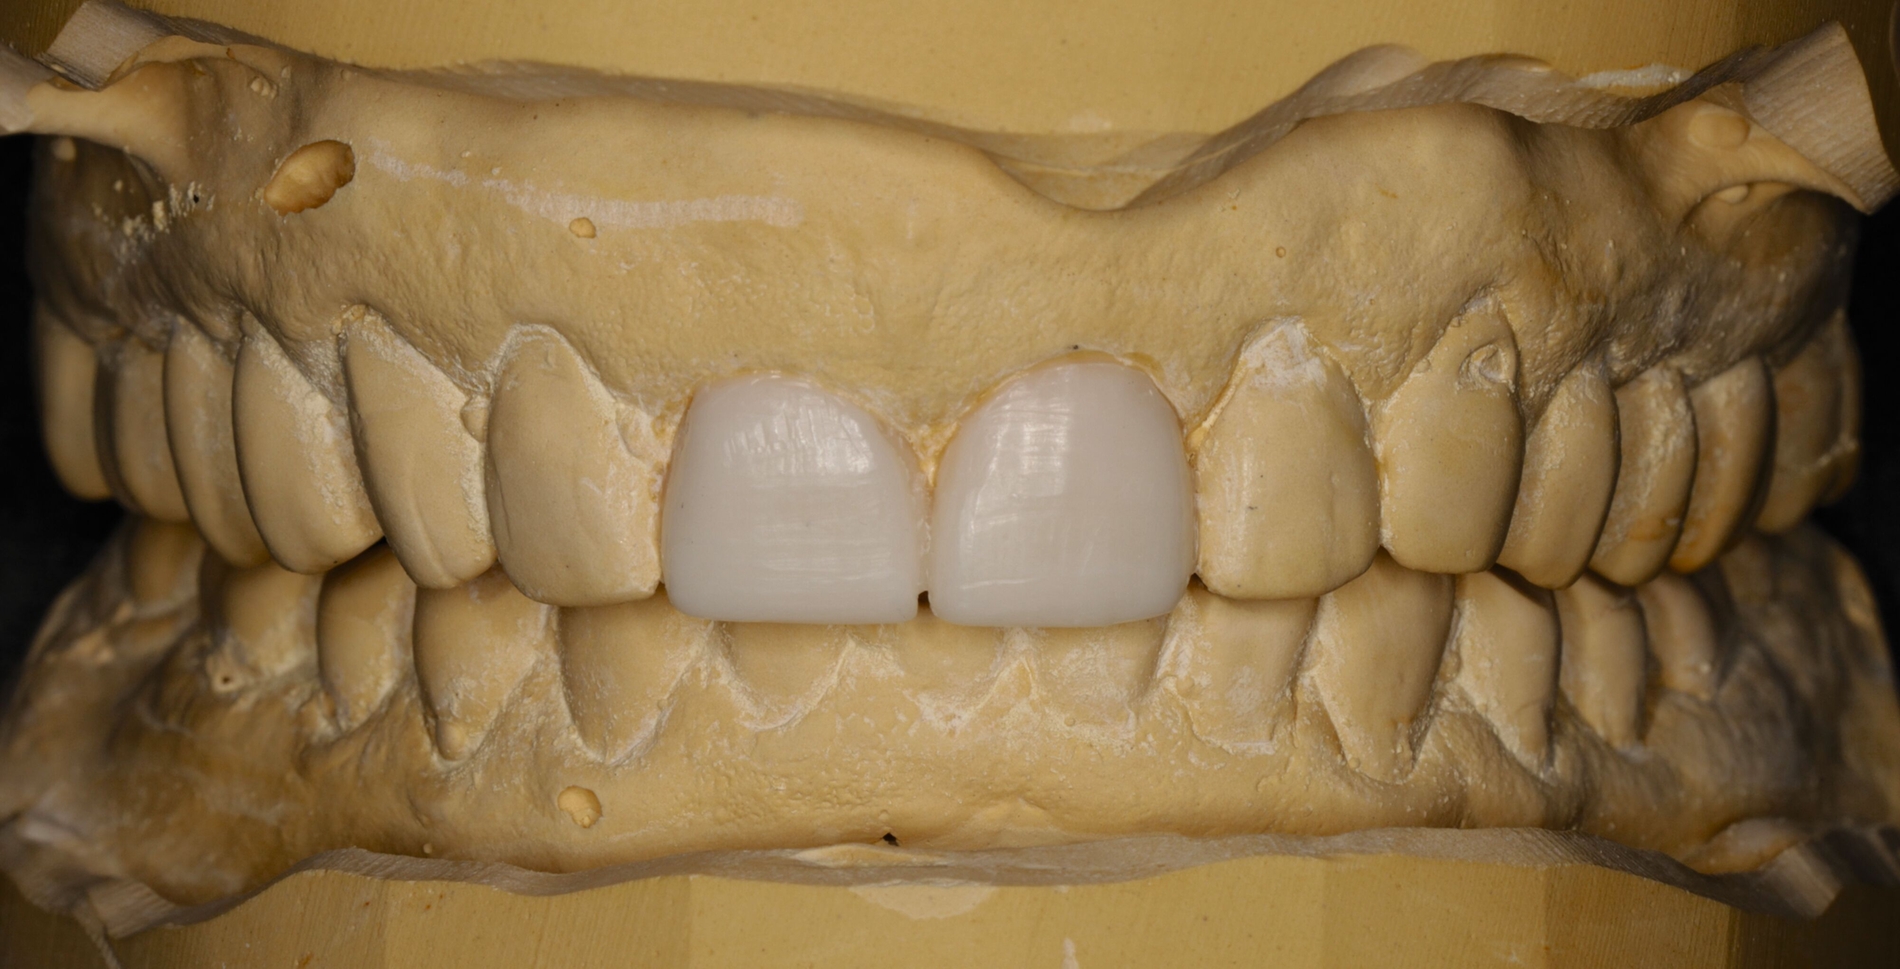

Nach Herstellung eines Wax-ups wurde zur Visualisierung des erzielten Ergebnisses und zur Kontrolle der Funktion ein intraorales Mock-up angefertigt (Abbildungen 4a bis 4d). Zur definitiven Versorgung wurden die Zähne 11 und 21 mit einem Universaladhäsiv im Etch & Rinse-Modus unter Verwendung eines Silikonschlüssels als Formhilfe sowie der Anlage von Frontzahnmatrizen (Unica anterior) mit direkten Kompositveneers in Inkrementschichttechnik restauriert (Abbildungen 4e bis 4g). Auf eine Gingivektomie zur Harmonisierung der Rot-Weiß-Ästhetik der elongierten Zähne 11 und 21 wurde auf Wunsch des Patienten verzichtet.

-> Der Vorteil der gewählten Frontzahnmatrizen liegt in der optimalen Visualisierung der finalen Form der Restauration und in der adäquaten Gestaltung der interproximalen Kontakte und zervikalen Ränder durch Gingivaretraktion [Urkande et al., 2023; Amaro et al., 2021].